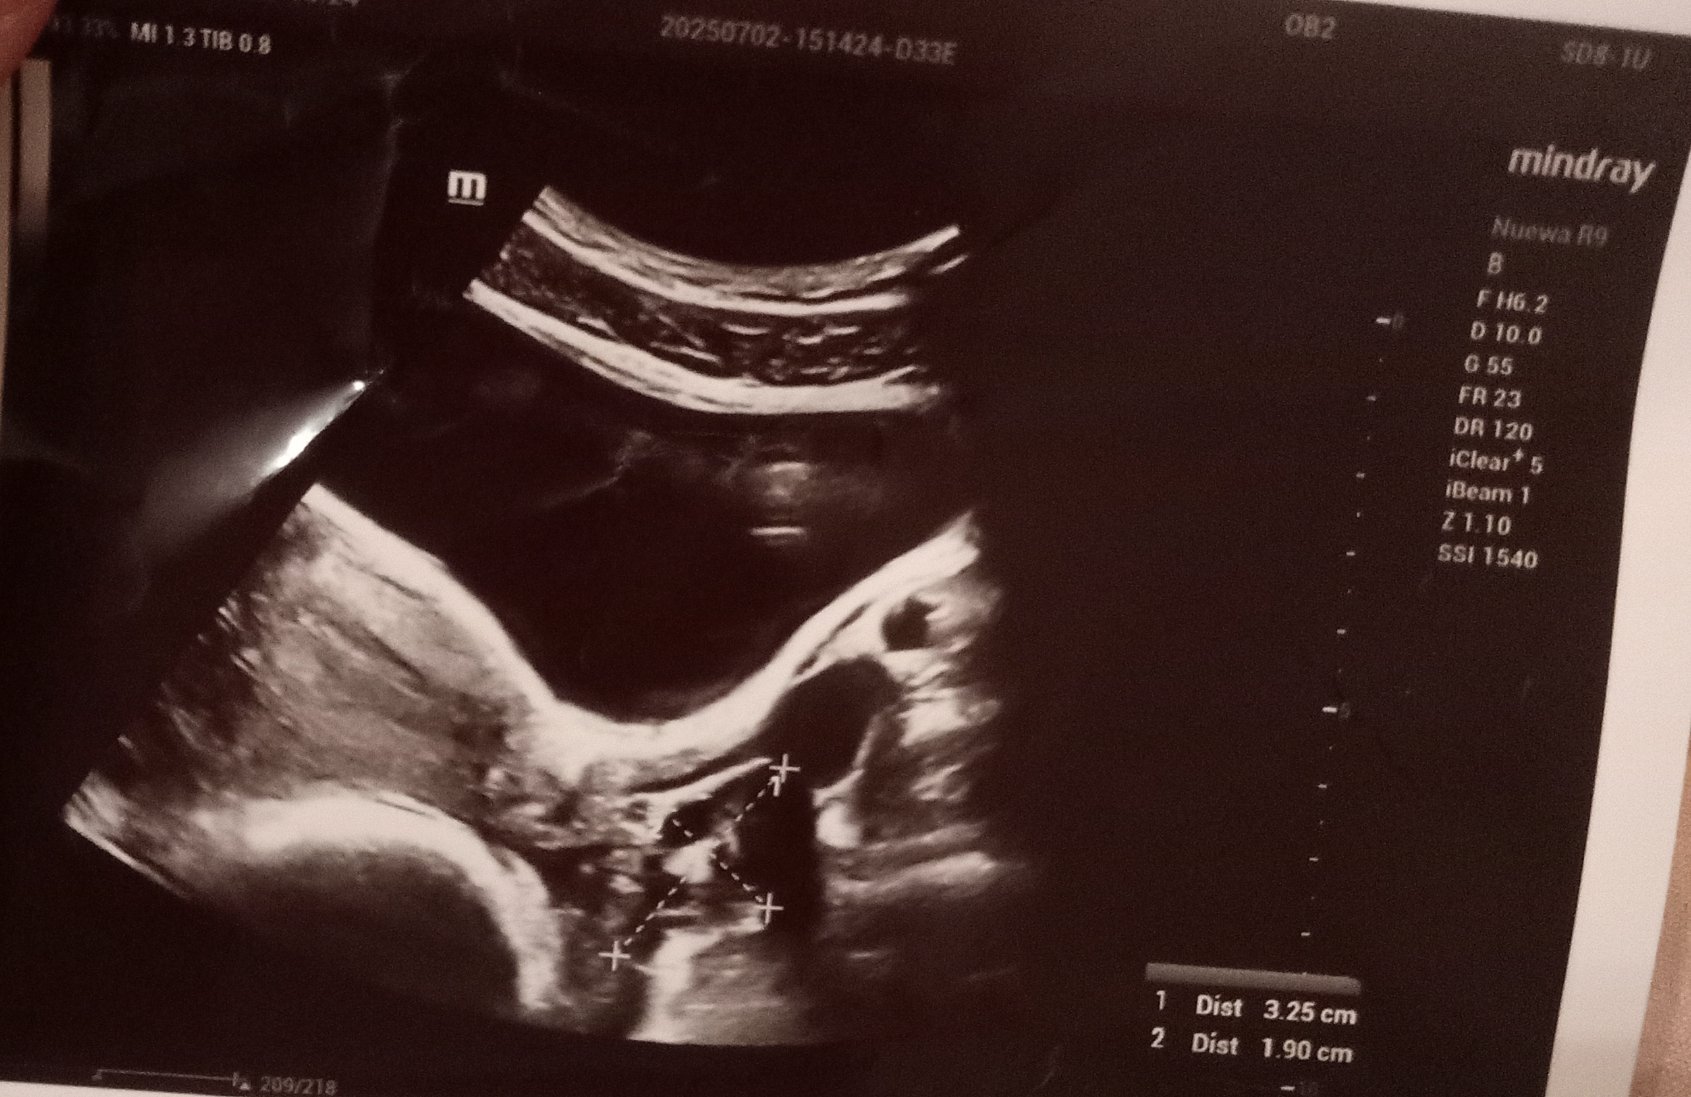

Ето и снимките от ехографа, какво мислите?

Скрит текст:

.